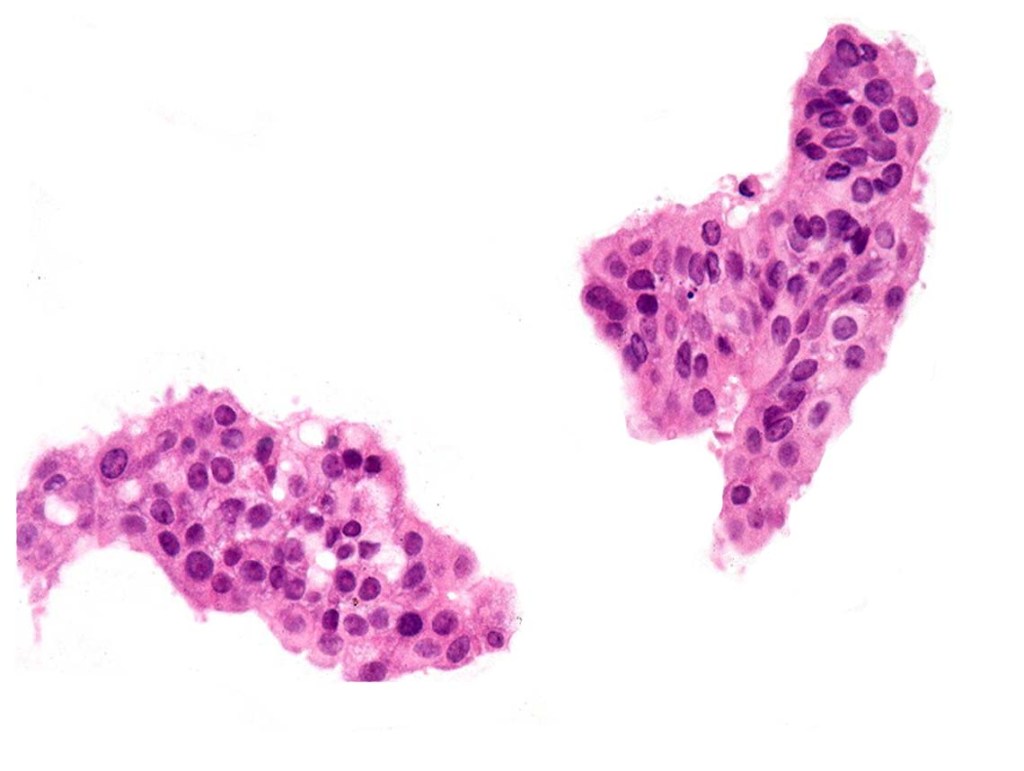

•EMPSGCa– multiple nodules of uniform epithelial cells with vesicular nuclei & small nucleoli

•In situ component sometimes evident

•+/- intracytoplasmic mucin

•Cyst formation sometimes evident

•Papillae & cribriform pattern sometimes evident

•+/- apocrine decapitation secretion

•No significant pleomorphism

•Few mitoses

•No abnormal mitoses